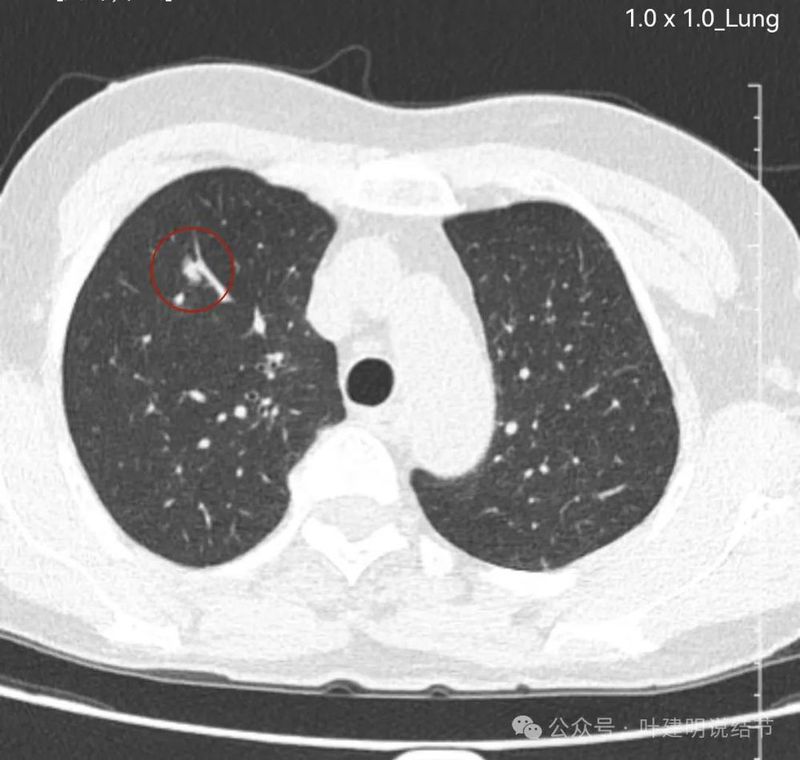

右下叶囊腔型病灶,囊壁较薄,内部有分隔,囊腔型肺癌不能完全除外,但肯定要先随访起。

右下另处囊腔灶,灶内有血管穿过,整体小且囊壁薄,再观察下。